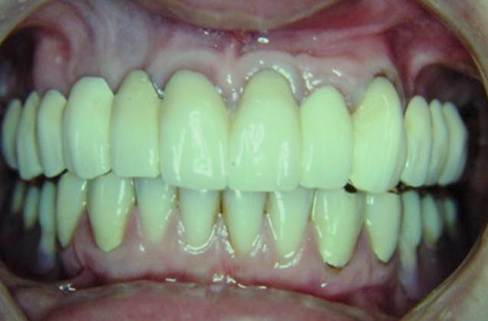

下のリーゲルテレスコープの途中経過。

そして、完成です。

ドイツで、35年前、Körber教授の指導の下、初めてのリーゲルテレスコープ症例を 行った私の思い出の症例です。